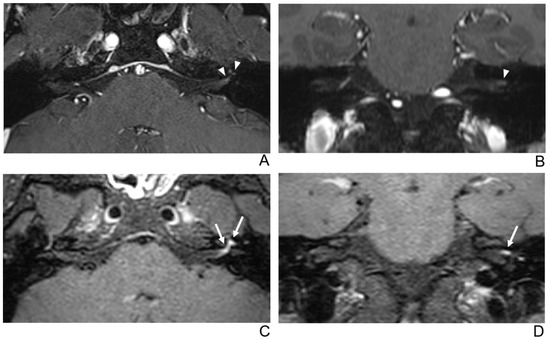

Figure 5.

A 68-year-old female without symptoms of facial palsy (normal control). (A–D) Paired axial and coronal CE-GRE (A,B) and T1 BB-FSE (C,D) images of bilateral facial nerves. The only distal canalicular segment of the left facial nerve demonstrates moderate asymmetric enhancement in the axial (A) and coronal (B) CE-GRE images (arrowheads); thus, each reviewer interpreted it as left facial neuritis (false positive; 1, diagnostic confidence; 2, visual grade for contrast enhancement in the canalicular segment). In contrast, the bilateral facial nerves showed no significantly asymmetric enhancement in the T1 BB-FSE axial (C) and coronal (D) images (arrows); two reviewers evaluated it as normal facial nerves (true negative).